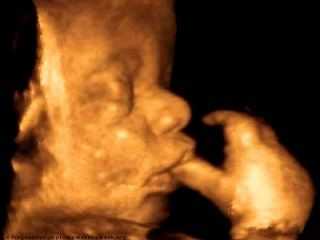

Развитие плода

Ваш малыш целиком и полностью уже подготовился для появления на свет. Абсолютно каждая из имеющихся систем, а также органов на 41 неделе беременности хорошо развиты. То есть малыш подготовлен для начала жизни вне утробы матери.

Внешнее развитие плода. Как он изменяется в этот период?

На данном сроке ребенок будет выглядеть гораздо красивее, нежели несколько месяцев назад. Сейчас родовая смазка находится лишь на нежнейших местах – в подмышках и пахе. Пушок пропал, а волосы на голове и ногти на пальцах растут. По этой причине совершенно не удивительно, когда ребенок рождается с хорошей шевелюрой и отросшими ноготками.

Детские формы становятся более круглыми, а вот хрящи ушей крайне плотными. Малыш прибавляет в сутки как минимум по 30 грамм жира. Его кожа розовая и гладкая. Плод на 41 неделе беременности уже весьма подрос и ему совершенно не комфортно в животе. По этой причине малыш периодически ведет себя тише и совершает крайне мало движений. Но все-таки вы по-прежнему обязаны чувствовать не менее десяти толчков ежедневно.